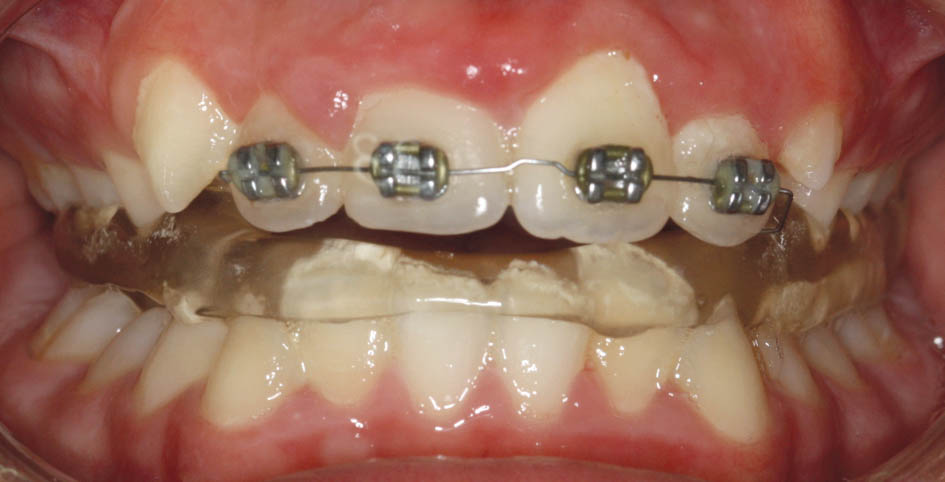

شکل 73-5: نمای روبروی بیمار

شکل 75-5: نمای روبروی بیمار